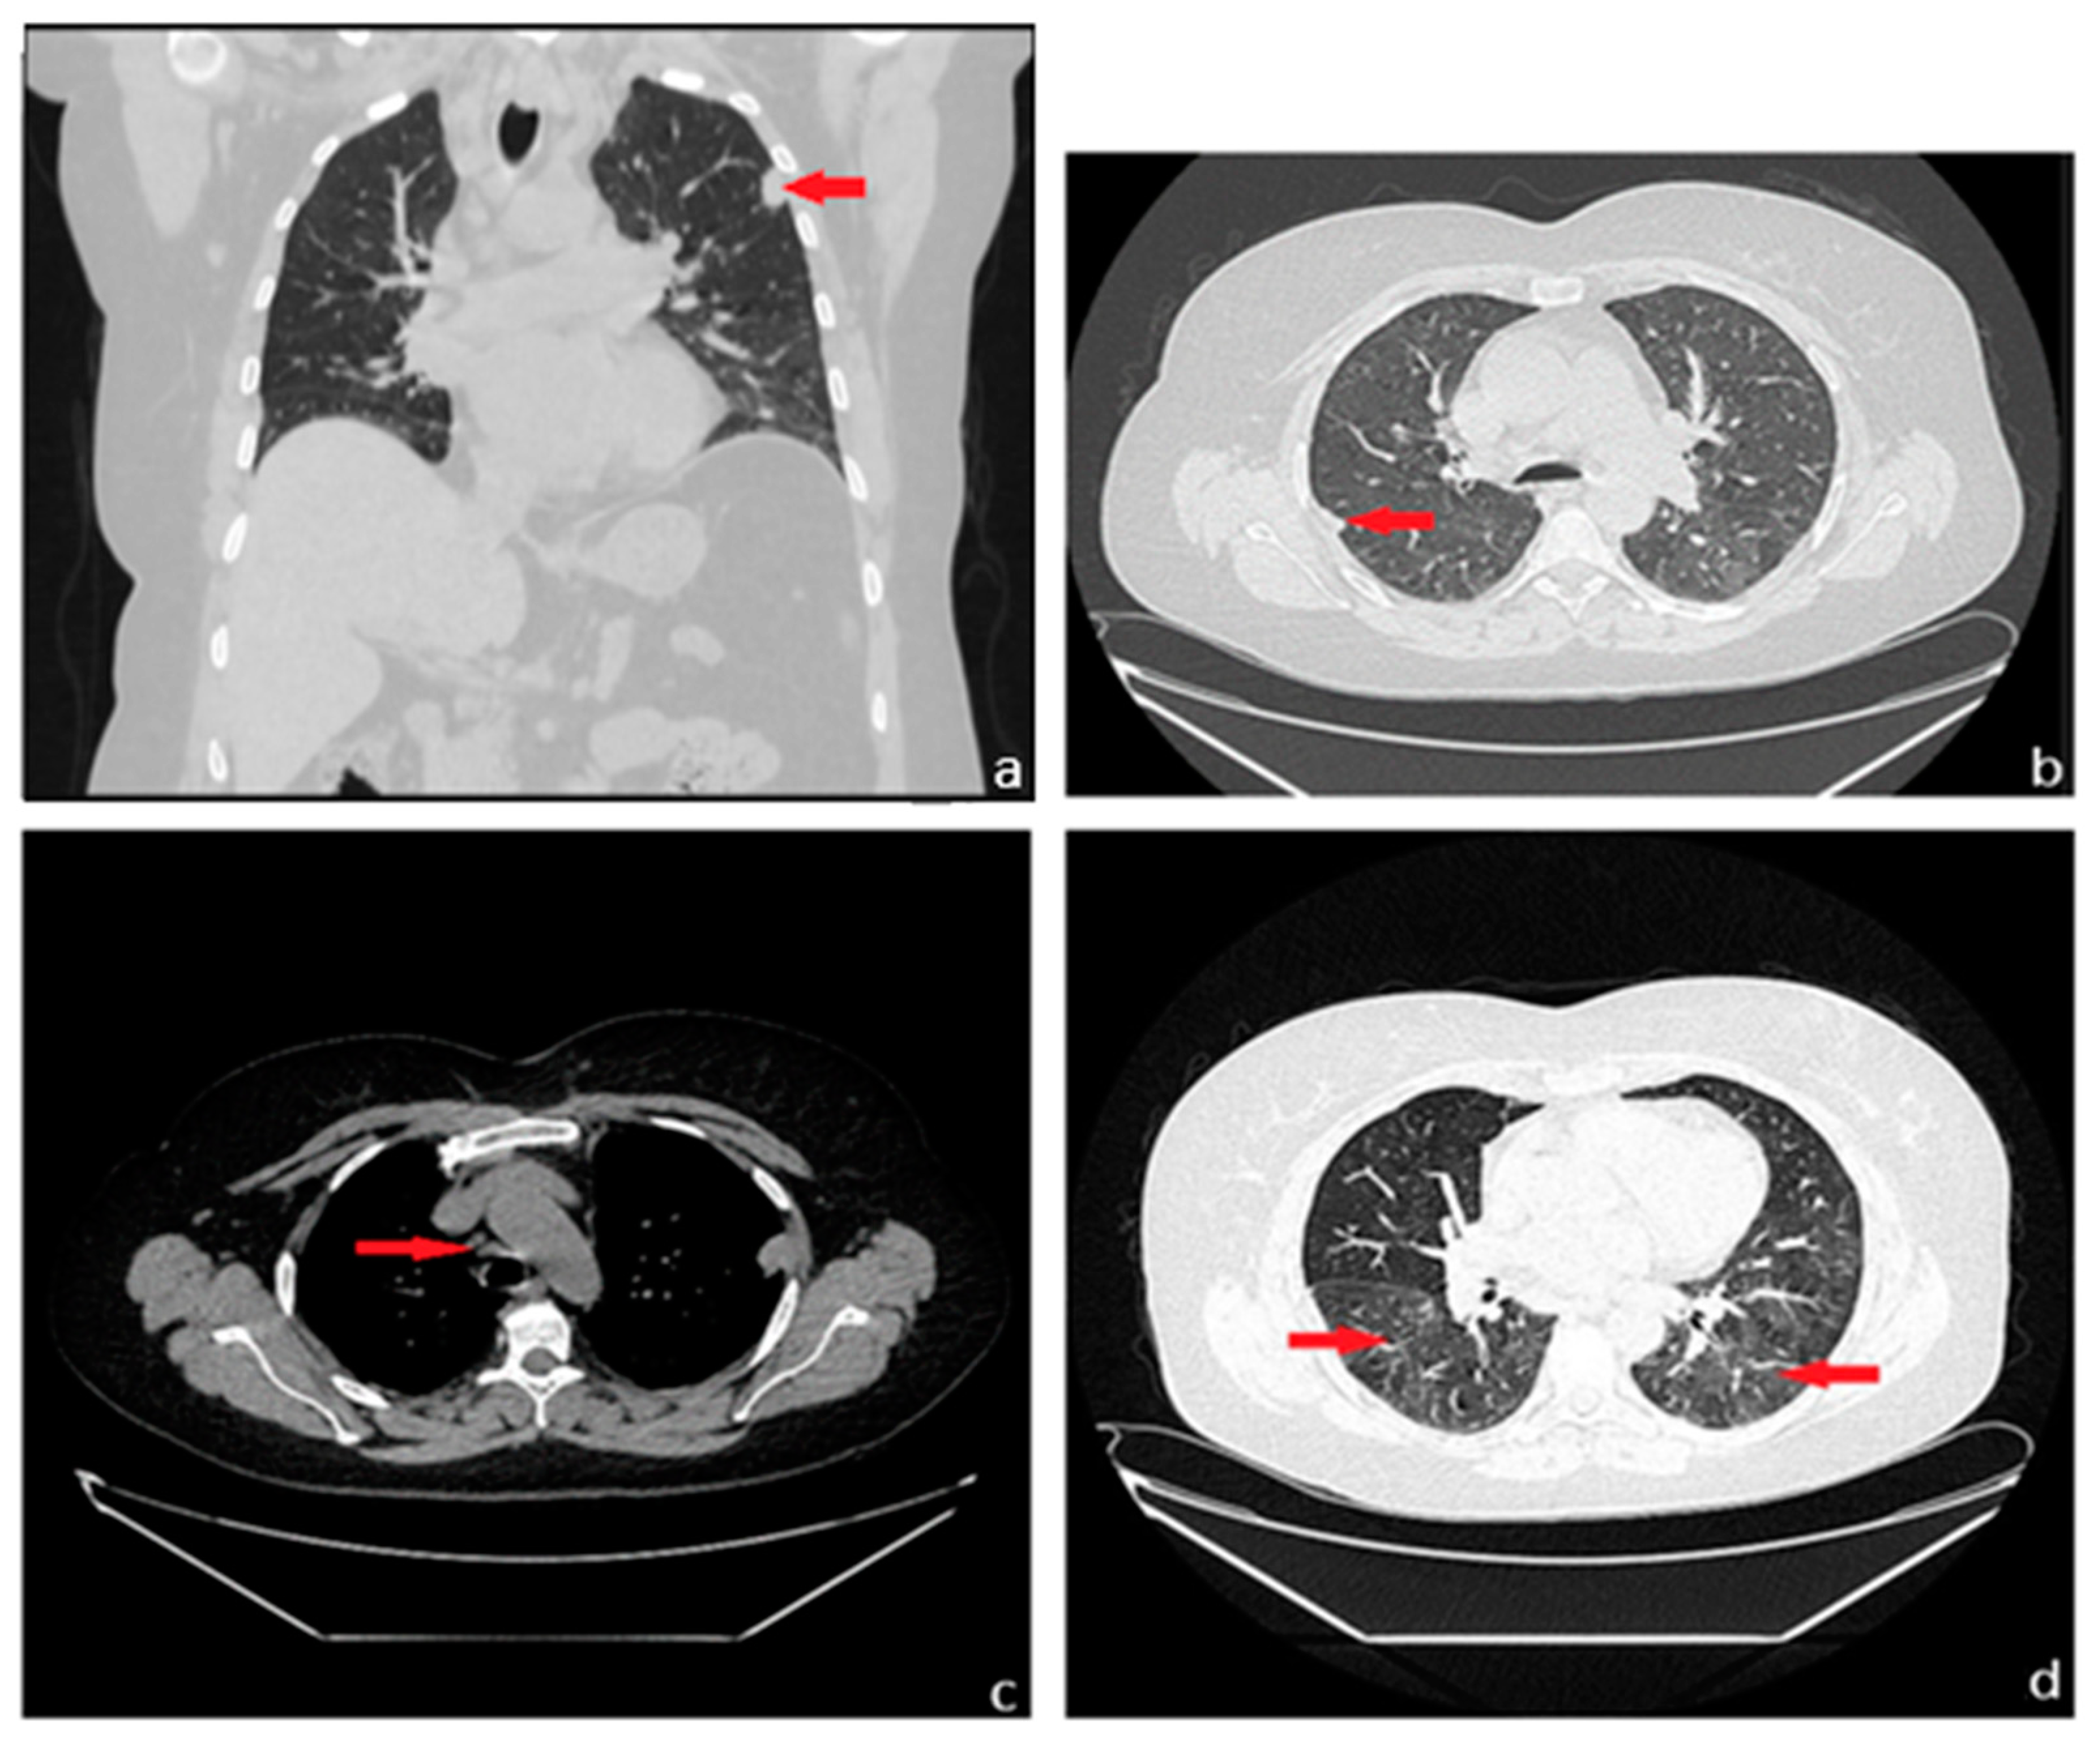

Figure 1. We present the case of a 59-year-old female patient, a former smoker with a history of 15 pack-years, who quit smoking 16 years ago, with prolonged occupational exposure to respiratory irritants (hairdresser for 23 years), who presented to our medical department for a detailed investigation of a lung nodule identified following examinations conducted at a regional medical facility. Her medical history up to this point showed no significant issues, except for a previous diagnosis of renal cysts and chronic treatment with antihypertensive medications (diuretics, angiotensin-converting enzyme inhibitors—ACE inhibitors, and central antihypertensives) for hypertension. In December 2022, she went to a regional medical care unit reporting mixed-type cough, predominantly irritative, with paroxysmal nocturnal exacerbations, moderate-effort dyspnea, and fatigue. Initially, symptomatology was labeled as residual from an acute upper respiratory tract infection. A chest X-ray was performed (Figure 1), which revealed a nodular pulmonary opacity (red arrow) of approximately 20/15 mm, located peripherally in the left upper lobe (LUL), adherent to the pleura, and an accentuated pulmonary interstitial pattern basal, bilaterally (blue arrow). Further, she was recommended to perform a spirometry with a bronchodilator test and additional imaging investigations with a contrast-enhanced chest computed tomography (CT) for accurate diagnostic assessment of the radiologically detected pulmonary nodule.